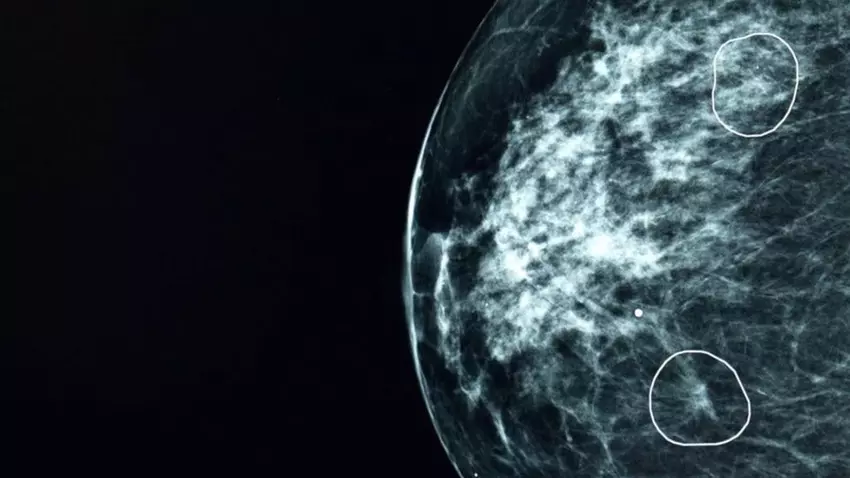

Tijdens tests in de National Health Service (NHS) van het Verenigd Koninkrijk heeft een kunstmatige intelligentietool genaamd Mia met succes bij 11 vrouwen tekenen van borstkanker geïdentificeerd die aanvankelijk door artsen werden gemist bij het analyseren van mammogrammen.

Bij het onderzoeken van meer dan 10.000 borstscans identificeerde Mia correct alle kankers die door artsen waren ontdekt en wees daarnaast 11 patiënten aan met minuscule tumoren van ongeveer 6 mm. In zo'n vroeg stadium is kanker vaak moeilijk met het blote oog te zien.

Een van deze 11 vrouwen is Barbara, wier tumor werd ontdekt door AI. Dankzij een tijdige diagnose had ze slechts een minimale behandeling nodig. Statistisch gezien heeft een tumor van minder dan 15 mm een overlevingskans van 90% binnen vijf jaar.